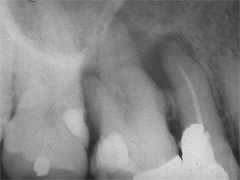

Aufbissempfindlichkeit an 33 veranlasste uns erstmalig in dieser Kieferregion zu röntgen. Mit grossen Augen sahen wir dann an, was uns auch ansah. Einen Knochendefekt dieser Grössenordnung mit seiner schaurigen Aura sieht man zum Glück nicht jeden Tag. Doch, obgleich das Alien dereinst Zahn 34 entsprang, war eine Behandlung nur am Zahn davor durchsetzbar. Dessen Wurzelfüllung erfolgte regulär nach 14 Tagen, neue Terminangebote aber wurden, weil angeblich nicht mehr nötig, verschmäht.

Keine 8 Wochen gingen noch in's Land, bis das mit Macht geschah, was lange schon erwartet war. Das Arbeitsprogramm bestand aus Eröffnung von Zahn 34 und einer Schwellung inkl. Drainage, am nächsten Tag dann noch Aufbereitung des Kanals mit Einlage. 2 Wochen später dann die Füllung plus einem als Resektion deklarierten Auslöffeln des Granu­lationsgewebes durch eine Mini-Öffnung, zu deren Verschluss eine Naht genügte.

3 Aufnahmen sind von 2001, die vierte vom Nov. 2006